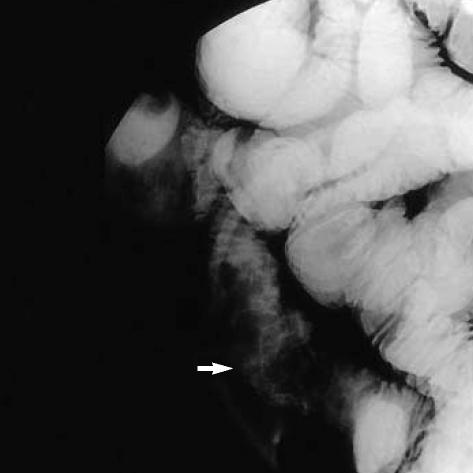

We report on an exceptional vascular cause of gastrointestinal hemorrhage. A 30-yr-old man was admitted because of recurrent hematochezia. Colonoscopy showed circumferential, erythematous, and nodular vascular distensions with hematocystic spots in the terminal ileum resembling varicosis and subsequent computed tomography with 3-dimensional angiographic reconstruction revealed a vascular architecture around the terminal ileum. No other potential source of bleeding was identified. The patient was treated by ileocecectomy and the final diagnosis was of an arteriovenous malformation confined to the terminal ileum. He has been followed up without a further hemorrhagic episode.